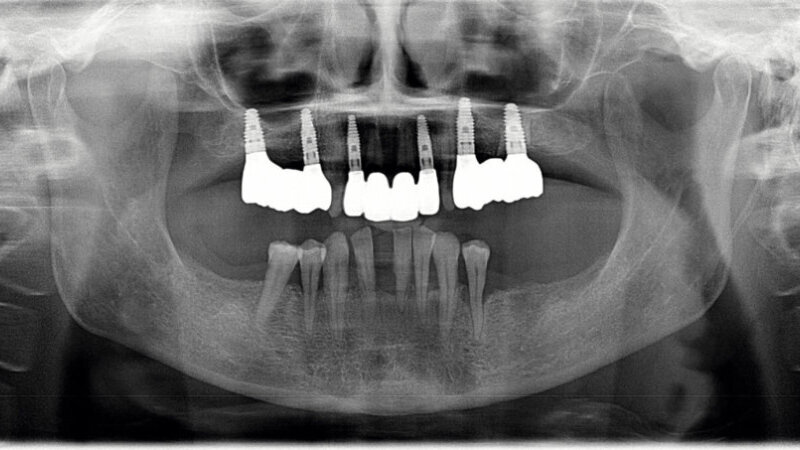

Slika 3. Inicijalni rendgenski nalazi prije početka liječenja.

58-godišnjakinja, nepušačica i sistemski zdrav pacijent kojeg je njen doktor dentalne medicine uputio u naš centar radi implanto-protetske terapije. Pacijenticu je uglavnom smetala loša estetika u gornjem frontalnom području, koje je karakterizirala visoka linija osmijeha i izražene anomalije položaja zuba (Slike 1. i 2.), kao i funkcionalna ograničenja kao posljedica neugode prilikom žvakanja. Tri zuba su nedostajala u gornjoj distalnoj regiji i to zubi 17, 15 i 27 koji nisu bili protetski opskrbljeni, dok je u donjoj čeljusti u distalnoj regiji nedostajalo pet zuba s obje strane u području premolara te su oni zamijenjeni djelomičnom mobilnom protezom. Svi preostali zubi u gornjoj i donjoj čeljusti bili su prema klasifikaciji „Proceedings of the World Workshop on the Classification of Periodontal and Peri-implant Diseases and Conditions 2017“ imali parodontitis stadija IV, a prosječna dubina sondiranja parodonta je bila 5,6 mm. 7 Prosječni indeks krvarenja (BOP) i srednji indeks plaka (PI) bili su 70 odnosno 80 posto. S obzirom na paradontološke parametre i mjere oralne higijene (vidljivi kamenac i naslage), oralna higijena pacijentice klasificirana je kao loša. Pacijentica je u drugoj ordinaciji liječena s dva implantata u desnoj maksilarnoj stražnjoj regiji kako bi se zamijenili prvi pretkutnjak i prvi kutnjak (Slika 3). Prema definiciji koju je Weißgold uveo 1977. godine, pacijent ima debeli biotip. 26